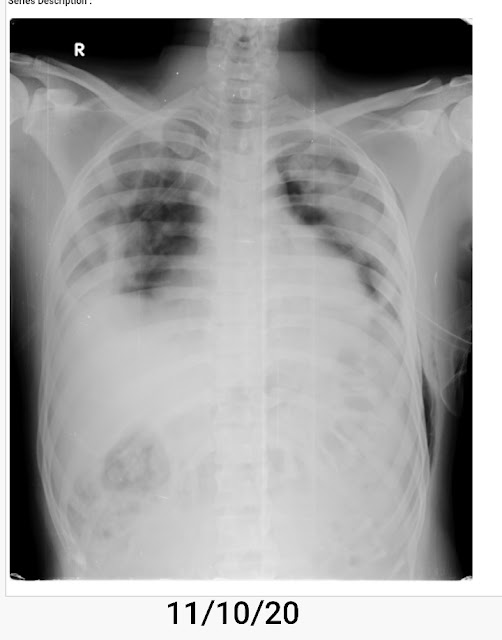

With the high clinical suspicion the treating doctors team ordered chest xray which revealed PNEUMOTHORAX

INTERCOSTAL DRAIN IS PLACED ON 11/10/20

Post procedure Xray